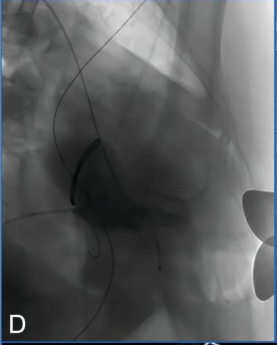

2. After successfully establishing the standard apical channel and securing the puncture site with a hexagonal suture technique, the angle was adjusted to a cranial right anterior oblique position for clearer visualization of the left ventricle and left atrium structures. Angiography was performed to assess the mitral regurgitation (Figure D), left ventricular morphology, and annulus structure.

Figure D: Intraoperative angiography indicated severe mitral regurgitation.